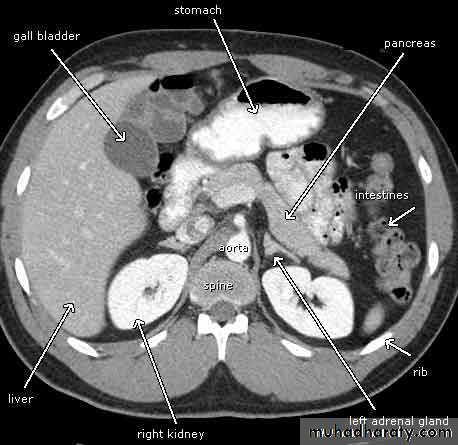

Pancreatitis

Patient present with abdominal pain , vomiting with or without jaundice , increase amylase level

CT finding

Enlargement of the pancreas focal or generalized increase in size .

Hypo density within the pancreas focal or generalized due to the edema .

Peri pancreatic fluid collection & edema around the pancreas .

The fluid around the pancreas if persist more than 6 w become encysted leading to the pancreatic pseudo cyst any area could be affected .

Edema of the wall of the stomach .